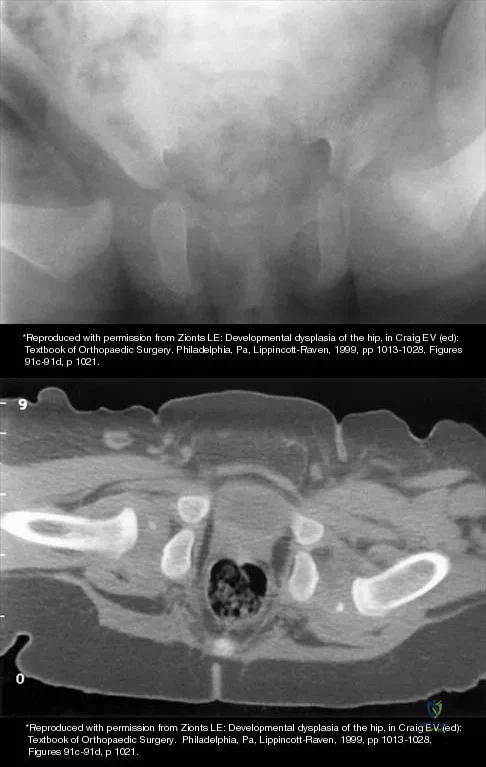

The mother of a 3-month-old infant states that she has difficulty positioning the infant's legs during diaper changes. Examination reveals limited abduction of both hips and a negative Ortolani sign. A radiograph reveals bilaterally dislocated hips. Initial management consists of guided reduction in a Pavlik harness, with weekly follow-up. Figures 57a and 57b show the radiograph and CT scan obtained after 6 weeks in the harness. Management should now consist of